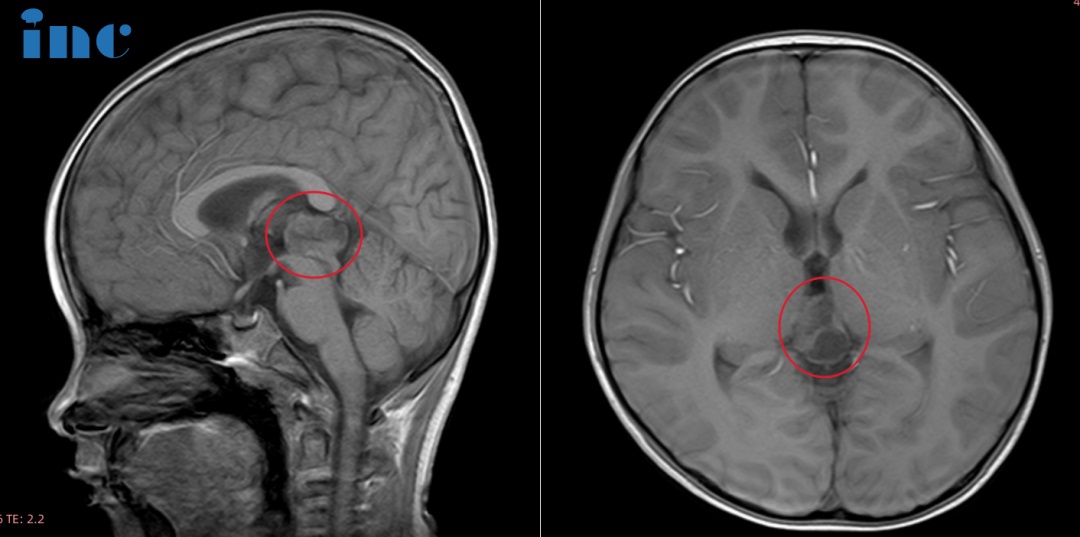

当日,由INC巴教授主刀,中德两国神经外科专家精诚协作完成了一台高难度的示范性手术。20岁,人生刚刚开始,应该努力奔跑、勇敢追梦的年纪,小峰不幸罹患脑干海绵状血管瘤,出血甚至还导致了肥大性下橄榄核变性(HOD),走路不稳、共济失调等。小峰的父亲不忍看到孩子承受着这些,便四处为他搜寻可以治疗的信息,幸运的是他们找到了巴教授。这位爱子心切的父亲在焦急等待着巴教授来华的过程中,也一直担心孩子会不会再次出血导致更严重的症状。

虽然出血已经部分吸收,但血管畸形仍在原地

巴教授40多年神经外科手术经验,30多年脑干手术经验,突破脑干这个“无人区”,将脑干海绵状血管瘤的手术升华到艺术之境。巴教授独特的手术技术,切除它而不引起新的神经功能障碍,不仅仅是医术上的创新,它改变的还包括众多病患一度难以挽回的绝望。本次手术的顺利完成让这位对未来充满美好憧憬的男孩重新获得了希望,这也是他人生中重要的转折点。目前小峰已经转入普通病房,整体状态良好,术前的症状也在逐渐好转。小峰的父亲看到孩子终于走出险境,庆幸之际也格外感恩,我们也祝愿他早日康复!